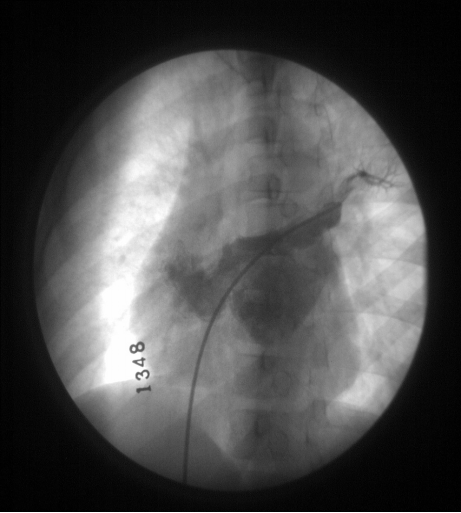

△ 左上肺静脉造影肝锁位显示继发孔型 ASD

△ 心血管造影已不是诊断ASD的常规方法

△ 在ASD封堵治疗时使用,但效果不如超声监测